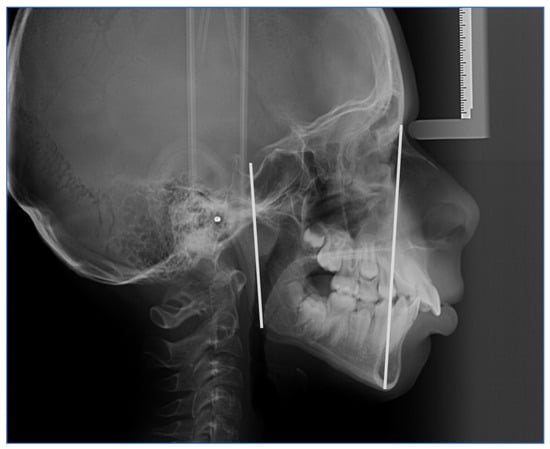

2.1.1. Cephalometric Measurements and Protocol

| 4 | S–Gn (y-axis) Angle | The mandible’s position in relation to the cranial base is defined. A mean value of 66° indicates a posterior mandibular position and a dominance of vertical growth; smaller angles indicate an anterior mandibular position and a dominance of anterior growth [20]. |

| 5 | Y SN Angle | Formed by the SN plane and the y-axis, it reflects the downward and forward posture of the chin relative to the upper face [21,22,23,24]. |

- S (sella turcica): located in the middle of the hypophyseal and pituitary fossae.

- N (nasion): the most anterior point of the middle frontonasal suture.

- Go (gonion): the midpoint on the posterior border of each gonial angle, located mediolaterally.

- Me (menton): the lowest point on the chin’s curve [25].